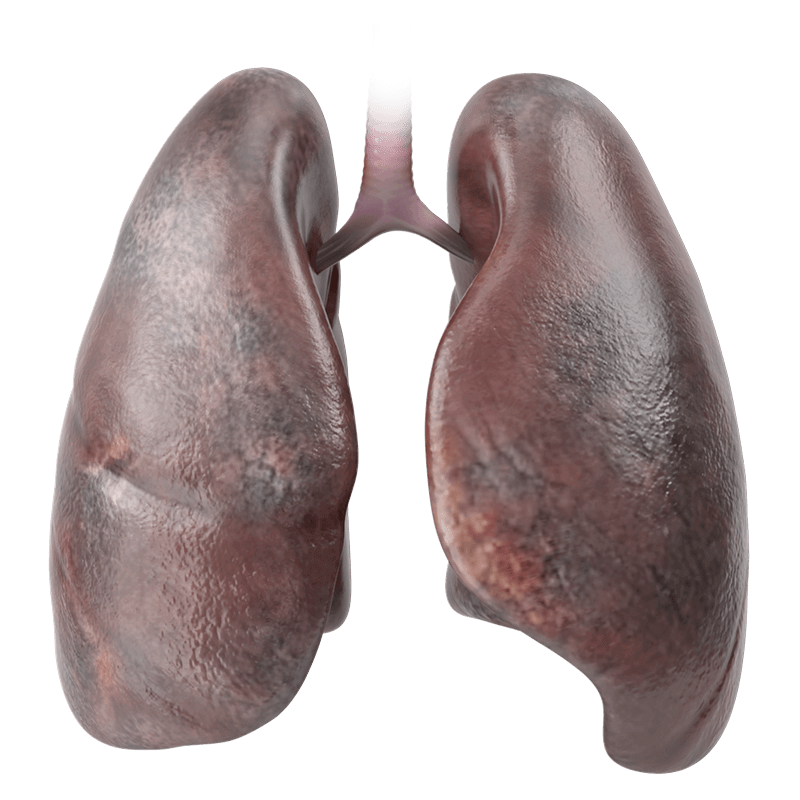

WHICH BODY PARTS CAN VAPING HARM?

The more studies are done, the more dangers are exposed. to see the vital organ damage connected to vaping.